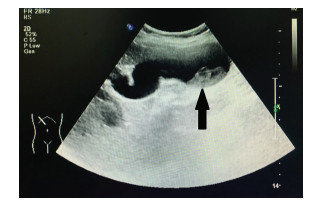

Primary splenic Kaposi sarcoma: A case report

Youchun LI, Guichao XU, Wenlei QI

2021, 37(7): 1668-1669. DOI: 10.3969/j.issn.1001-5256.2021.07.038

Abstract(891) HTML (222) PDF (2767KB)(51)

Abstract: